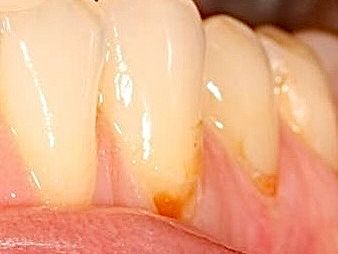

• Лечением кариозных поражений всех стадий, а также их осложнений, таких как пульпиты и периодонтиты.

• Профессиональной гигиеной полости рта, включая снятие зубного камня и пигментированного налёта с использованием современного оборудования.